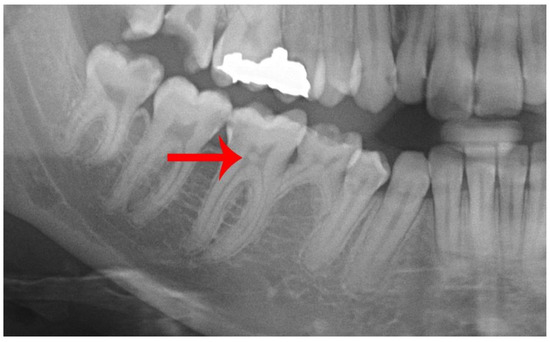

2.2. Radiograph Evaluation